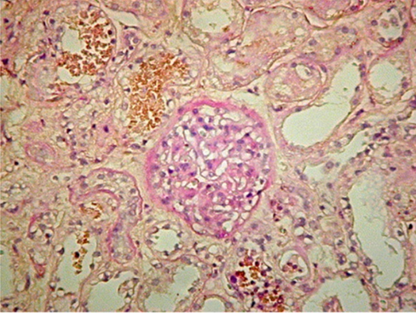

图3.一例口服柏木热水提取物后急性肾损伤的组织学图片

与中草药相关的肾毒性包括AKI、CKD、肾结石、横纹肌溶解症、范可尼综合征和尿路上皮癌。